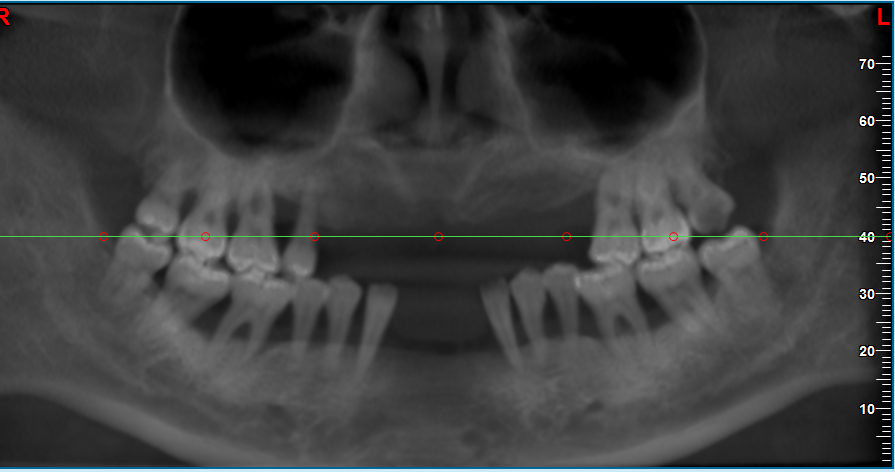

1、合肥美奥口腔的种植牙医生团队由多位口腔医学博士及高难度种植医生组成,临床经验均超过10年,擅长处理全口/半口缺牙、骨增量修复等复杂病例。医生团队采用3D CBCT扫描与数字化导板技术,实现0.1mm级种植精度,显著降低手术风险。

2、数字化导板技术:通过三维影像重建,稳准定位种植体位置,避免盲种操作,术后周期缩短30%以上。